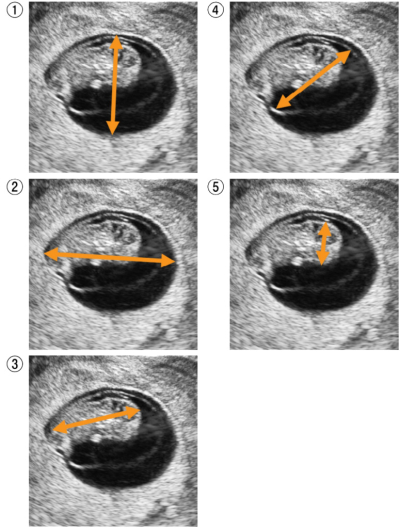

妊娠初期の経腟超音波像を別に示す。分娩予定日を決定するために有用な計測部位はどれか。

頭殿長(CRL)で分娩予定日を決定する。